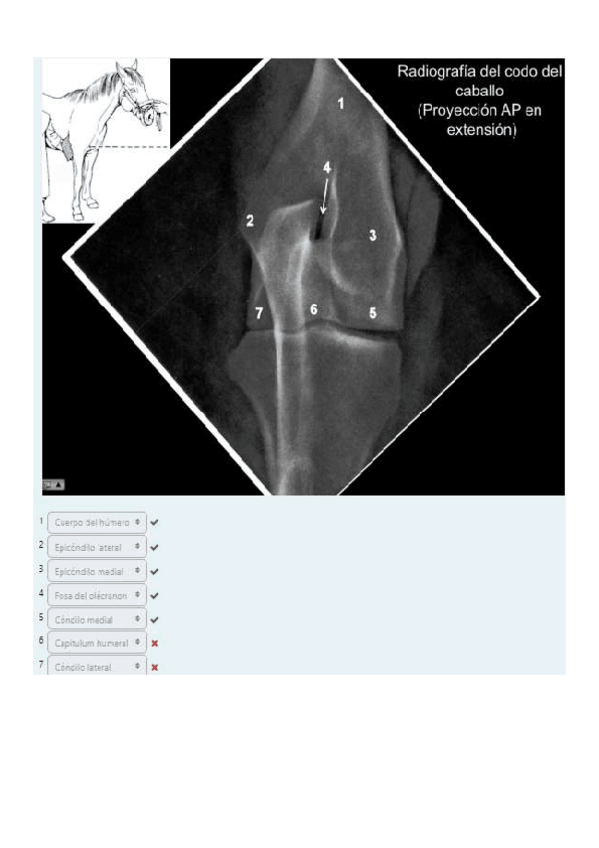

He publicado nuevos apuntes de 1º EMBRIOLOGÍA Y ANATOMÍA I: Radiografías práctica 6.pdf

8 páginas

He publicado nuevos apuntes de 1º EMBRIOLOGÍA Y ANATOMÍA I: SOLUCION-RADIOGRAFIAS-COMPLETAS.pdf

61 páginas

He publicado nuevos apuntes de 1º EMBRIOLOGÍA Y ANATOMÍA I: Todas-las-radiografias-de-anatomia-para-estudiar.pdf

129 páginas

He publicado nuevos apuntes de 1º EMBRIOLOGÍA Y ANATOMÍA I: TEST-8-radiografias-corregido.pdf

12 páginas

He publicado nuevos apuntes de 1º EMBRIOLOGÍA Y ANATOMÍA I: TEST-3-radiografias-corregido.pdf

5 páginas